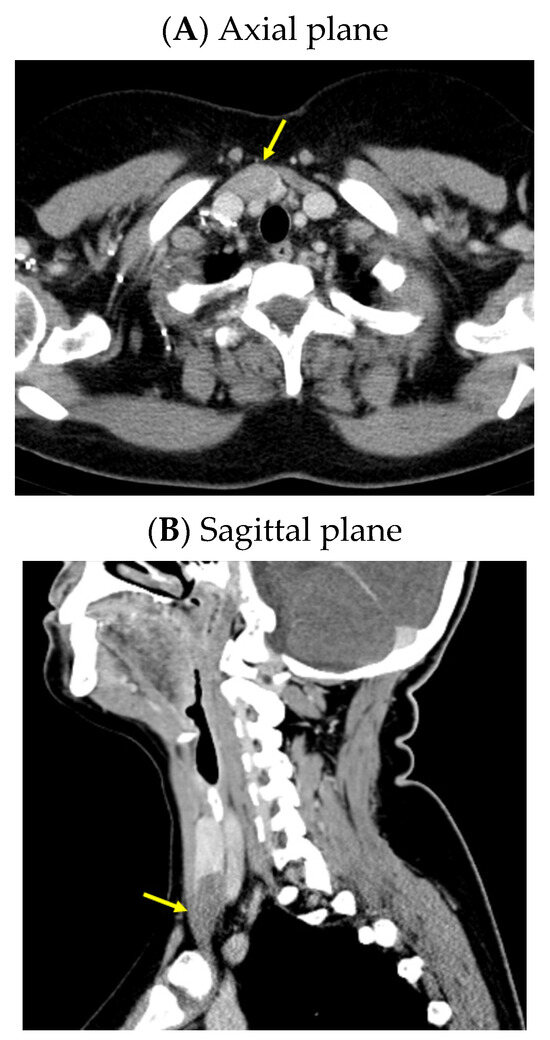

An anterior neck ultrasound revealed that posterior and inferior to the right thyroid lobe, a hypoechoic, inhomogeneous, and highly vascularized nodule of 3.98 by 1.13 by 2.53 cm was found, suggestive of a right inferior parathyroid tumor. Furthermore, a right thyroid lobe of 1.70 by 1.36 by 5.25 cm and a left thyroid lobe of 1.60 by 1.12 by 5.11 cm with a hypoechoic, inhomogeneous, micronodular pattern and normal vascularization were identified; the isthmus was of 0.35 cm with a hypoechoic, inhomogeneous nodule of 1 by 0.50 by 0.97 cm. A computed tomography (CT) scan confirmed the single parathyroid tumor (a hypodense nodule of 2.48 by 1.80 by 3.69 cm) (Figure 1).

Figure 1.

Intravenous contrast CT scan: right inferior parathyroid tumor (yellow arrow) displayed as a hypodense nodule of 3.98 by 1.13 by 2.53 cm.

A CT scan confirmed the rib tumor mass (highly suggestive of a brown tumor) located in the middle and posterior part of the left sixth rib that caused median cortical destruction (of 3.09 by 5.13 cm in the axial plane, 2.53 by 3.31 cm in the coronal plane reconstruction, and 6.11 by 3.46 cm in the sagittal plane reconstruction) (Figure 5).

Figure 5.

Intravenous contrast CT: a tumor mass located in the middle and posterior part of the left sixth rib, with median cortical destruction of 2.53 by 3.31 cm, suggestive of a brown tumor (yellow arrow).